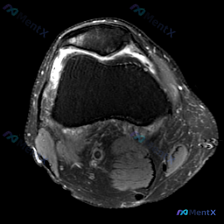

病例基础信息 这是一份仅提供单张踝关节MRI轴位T2加权扫描图像的读片讨论,用户提问「这幅图里明显能看到什么?提示软组织积液」,我们先整理原始影像分析结果: 1. 解剖结构评估: - 骨骼:胫骨远端、腓骨远端、距骨穹窿部结构正常,骨皮质、骨髓腔信号无明显异常,无骨折、骨质破坏 - 肌腱:胫骨后肌腱、...